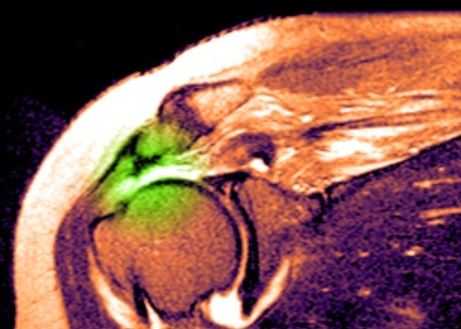

МРТ плечевого сустава. Т2-взвешенная корональная МРТ. Разрыв вращательной манжеты. Цветовая обработка изображения.

Анатомия плечевого сустава. Т1-зависимая МРТ в корональной плоскости. Обозначения: 1 -суставная (гленоидная) впадина, 2 - ключица, 3 -головка плечевой кости, 4 - подлопаточная мышца, 5 - дельтовидная мышца, 6 - длинная головка сухожилия двуглавой мышцы плеча, 7 - надостная мышца, 8 - трапецевидная мышца, 9 - сухожилие надостной мышцы, 10 - верхняя губа.

При МРТ плечевого сустава косвенным признаком разрыва вращательной манжеты служит высокий сигнал на Т2-взвешенных от поверхности сустава до субакромиальной (субдельтовидной) сумки. Частичные разрывы чаще всего по передней поверхности сухожилия м.supraspinatus, реже примыкая к большой бугристости или сухожилия м. infraspinatus.